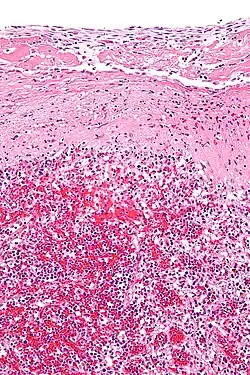

En el uso médico histopatológico, una sustancia hialina aparece vidriosa y rosada después de teñirse con hematoxilina y eosina, por lo general, es un material acelular y proteináceo. Un ejemplo es el cartílago hialino, un cartílago articular transparente y brillante.[3]